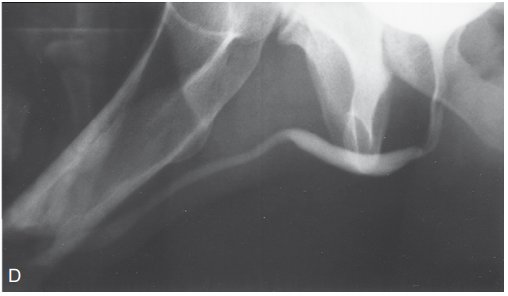

• Уретрографія – рентгенологічне дослідження з контрастом.